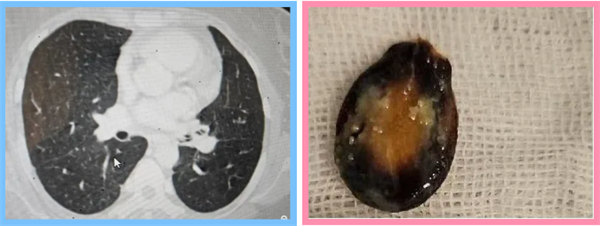

絕望之際,張先生來到了寶雞市人民醫(yī)院呼吸與危重癥醫(yī)學(xué)一科。面對張先生的復(fù)雜病情,科主任王惠霞詳細(xì)詢問了病人情況,與主管醫(yī)生呂天樂對其進(jìn)行體格檢查以及高分辨率CT和支氣管鏡等先進(jìn)檢查手段綜合應(yīng)用,終于發(fā)現(xiàn)了隱藏在氣管內(nèi)的“真兇”——那粒導(dǎo)致張先生長期咳嗽、咳痰和喘息的瓜子。

確診后,呼吸與危重癥醫(yī)學(xué)一科團(tuán)隊(duì)迅速制定了個性化的治療方案,并成功通過支氣管鏡手術(shù)將瓜子取出。隨著異物的清除,張先生的癥狀迅速緩解,咳嗽喘息癥狀逐漸消失。